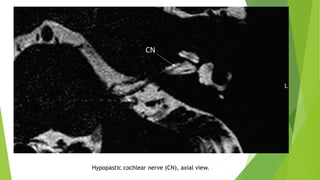

Hypopastic cochlear nerve (CN), axial view.

2- Hypoplastic CN

There is a separate CN but the size is less than the contralateral normal CN or

ipsilateral normal facial nerve